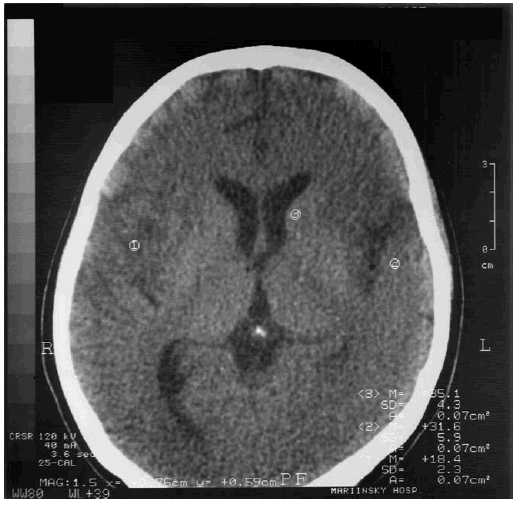

Пациентам с герпетической инфекцией показаны противогерпетические препараты; один из наиболее эффективных – зовиракс (ацикловир), подавляющий продукцию новых вирусов и развитие пузырьков. При появлении герпетических пузырьков на места поражения сразу наносится мазь ацикловир, по назначению врача применяют таблетки ацикловира. Больным с герпетическим энцефалитом ацикловир назначается внутривенно как можно раньше, введение его спустя пять дней после начала болезни существенно снижает лечебный эффект. В исходе герпетических энцефалитов часто развиваются грубые нарушения когнитивных функций, что объясняется преимущественным поражением лобных и височных областей головного мозга с развитием кистозно-атрофических изменений. На рис. 9.1 представлена МРТ головного мозга пациентки 22 лет с деменцией после перенесенного герпетического энцефалита. Деменция у таких пациентов характеризуется выраженными расстройствами мышления, памяти, поведенческими нарушениями, ассоциированными с речевыми расстройствами (смешанная афазия, моторная, сенсорная афазия), центральными парезами. При нейропсихологическом обследовании пациентов с герпетическим энцефалитом наиболее часто выявляются амнестическая афазия, нарушения праксиса, гнозиса [75]. Такие пациенты нуждаются в длительной реабилитации с включением в комплексную терапию реминила, акатинола мемантина.

Рис. 9.1. МРТ головного мозга пациентки с деменцией после перенесенного герпетического энцефалита